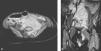

RM abdominal, secuencias STIR en los planos axial (A) y coronal (B). Se observa una gran masa retroperitoneal (*) polilobulada, situada en la línea media y lateralizada mayoritariamente hacia la izquierda, que se extiende hacia la pelvis y que desplaza y colapsa parcialmente los grandes vasos: la vena cava inferior, la aorta y los vasos ilíacos. Las medidas son 99×59×62cm (craneocaudal-anteroposterior-transverso). En A se introduce por el agujero de conjunción de L5-S1 izquierdo (flecha) y ocupa el conducto raquídeo, y en B por el orificio inguinal interno izquierdo (flecha).